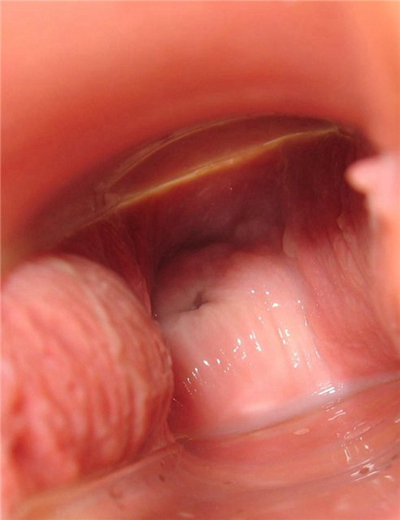

子宮肥大圖片

子宮肥大圖 (7)

子宮肥大圖 (8)

子宮肥大圖 (9)